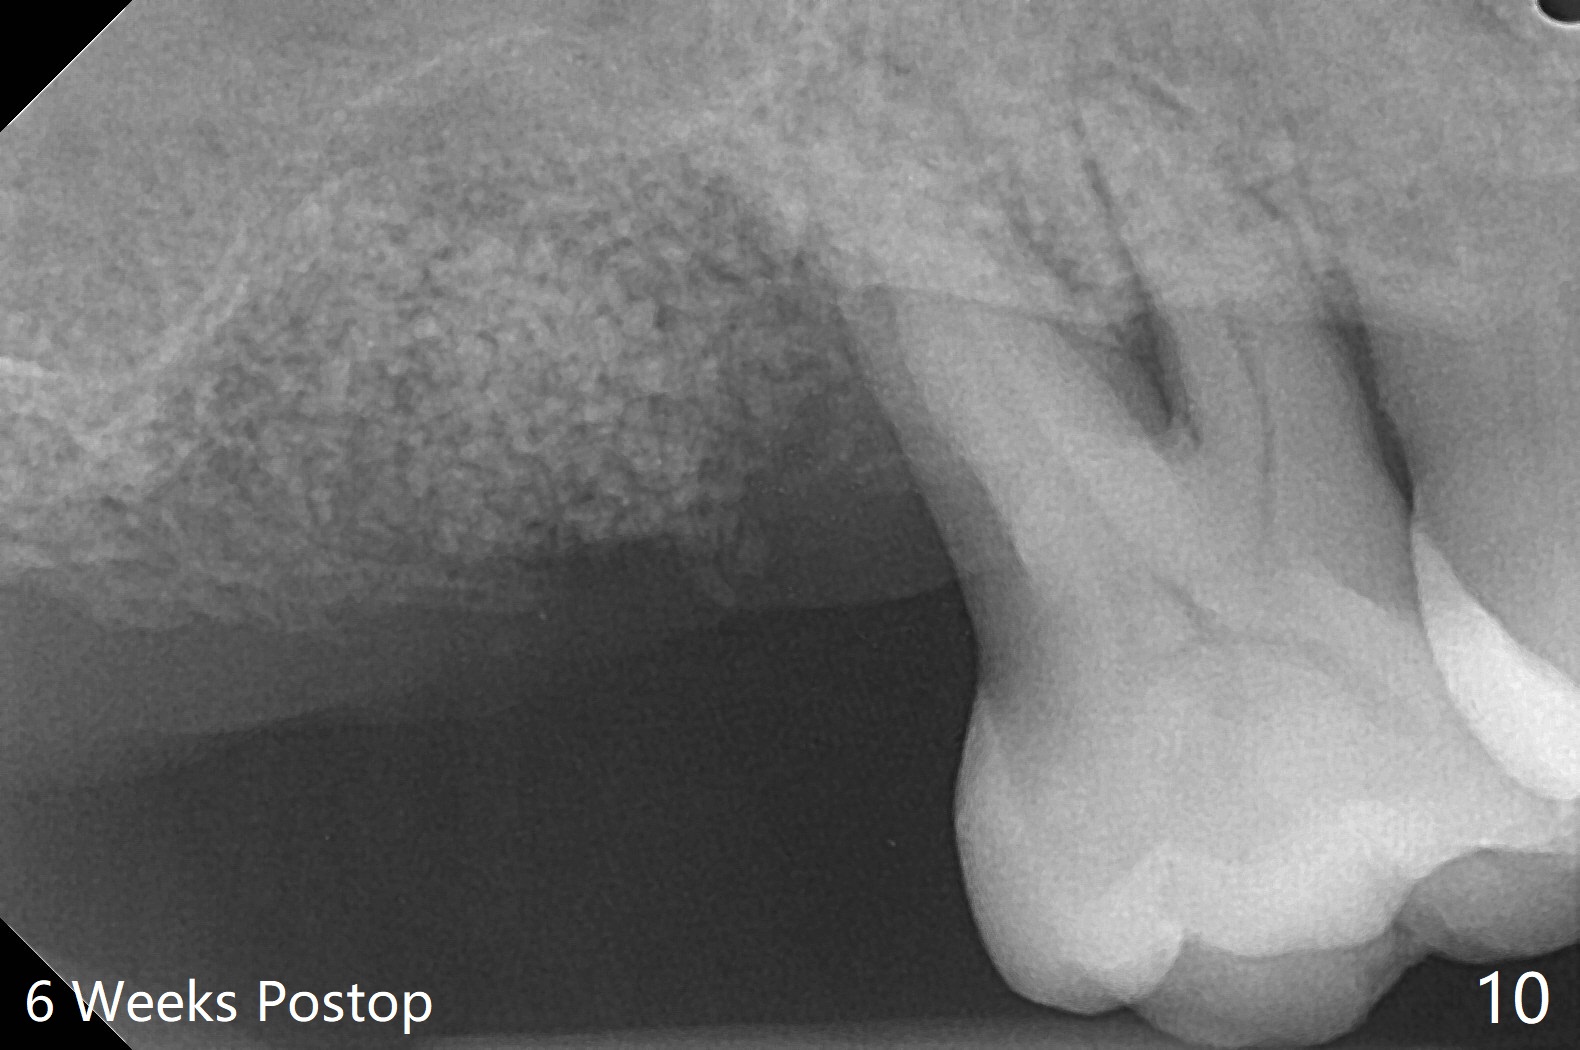

尽管右上第一,二磨牙骨质吸收严重,为了保持牙乳头,先拔除有症状第二磨牙,但是后者牙槽窝与第一磨牙之间好像没有软组织(图二:*),所以骨粉(图一,二:7)无法从前者推入后者(图二(下一个成功病例))。骨粉表面放置6个月吸收膜(GEM Cap(图三::C)),使用牙周胶水固定,而且装置牙齿空间维持器(图二:S)和牙周敷料强化固位。牙齿拔除证实腭侧牙槽窝(图四:P)上颌窦底板穿孔(^;但是没有漏气)。虽然病人已经服用Amoxicillin一周以及Z Pack(两颗,术前),为了防止感染介入上颌窦,穿孔冠部放置胶原塞(图五:黄色),然后放置骨粉(红色)。后者仿佛增加骨质高度不少(图二)。如果不够,以后再做提升。多亏间隙保持器,牙周敷料术后4天没有松动迹象(图六)。术后三周敷料颊侧有些破裂(图七),而舌侧完整(图八)。嘱咐病人正常刷牙和水牙线,让敷料自行脱落。其实术后六周敷料仍在原位,不可吸收膜粘附于敷料,两者一起去除,伤口愈合(图九),骨粉好像没有损失(图十)骨高度减少。术后4个月骨质高度继续减少(图十一)。植骨后骨质高度还与邻牙一致,密度低,可植入5x7.3毫米植体(图十二)。